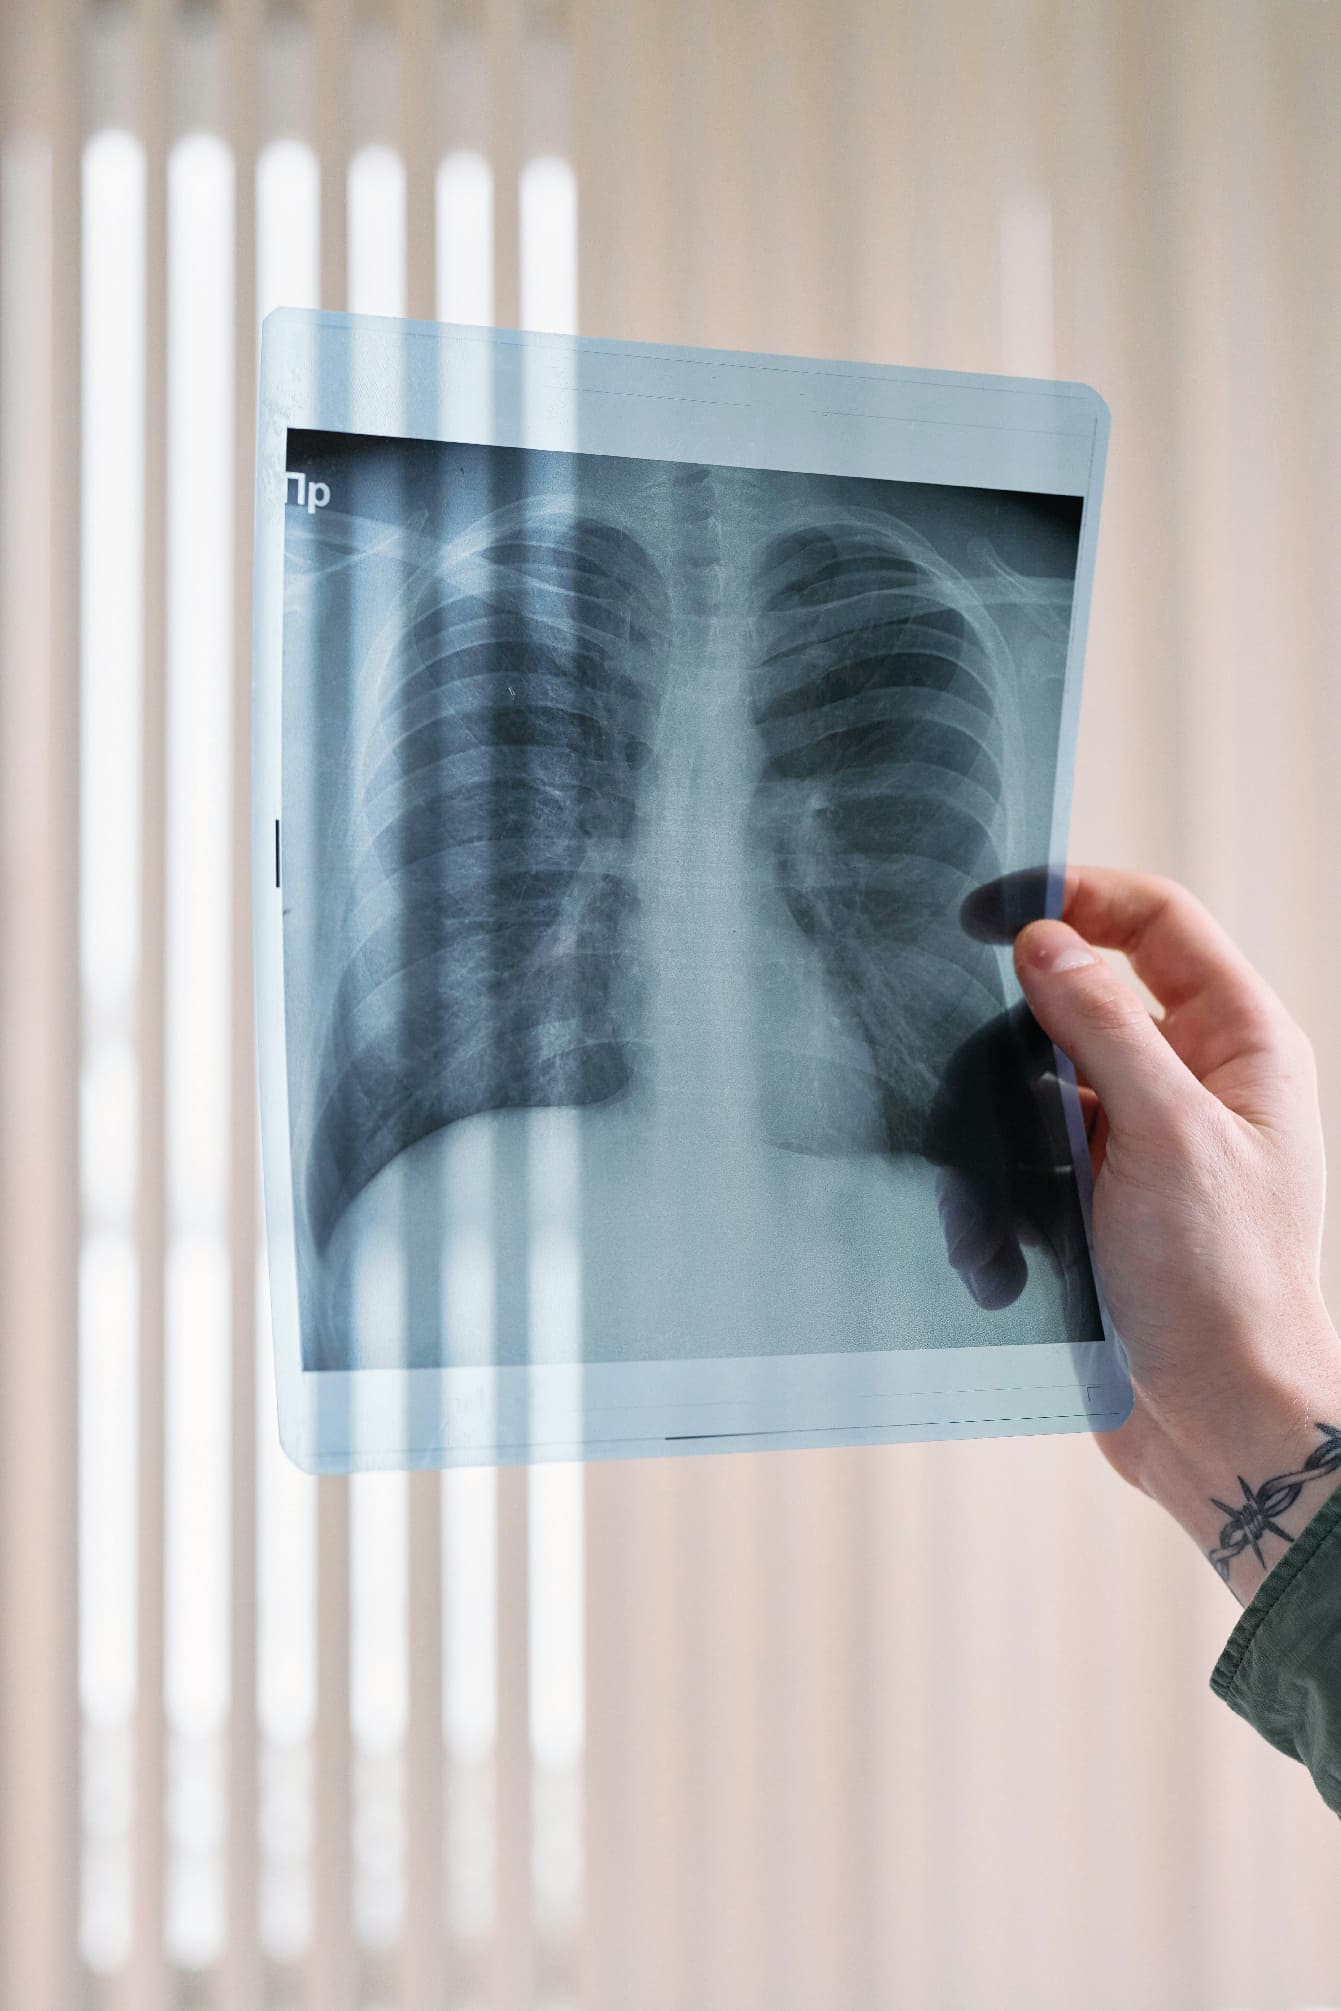

Estudios Diagnósticos

Solicito pruebas de laboratorio y radiografías para un diagnóstico preciso y confiable.

Bronquiolitis

Inflamación de las vías respiratorias inferior común en bebés.

Asma pediátrico

Enfermedad crónica de las vías respiratorias.

Neumonía

Infección de los pulmones.